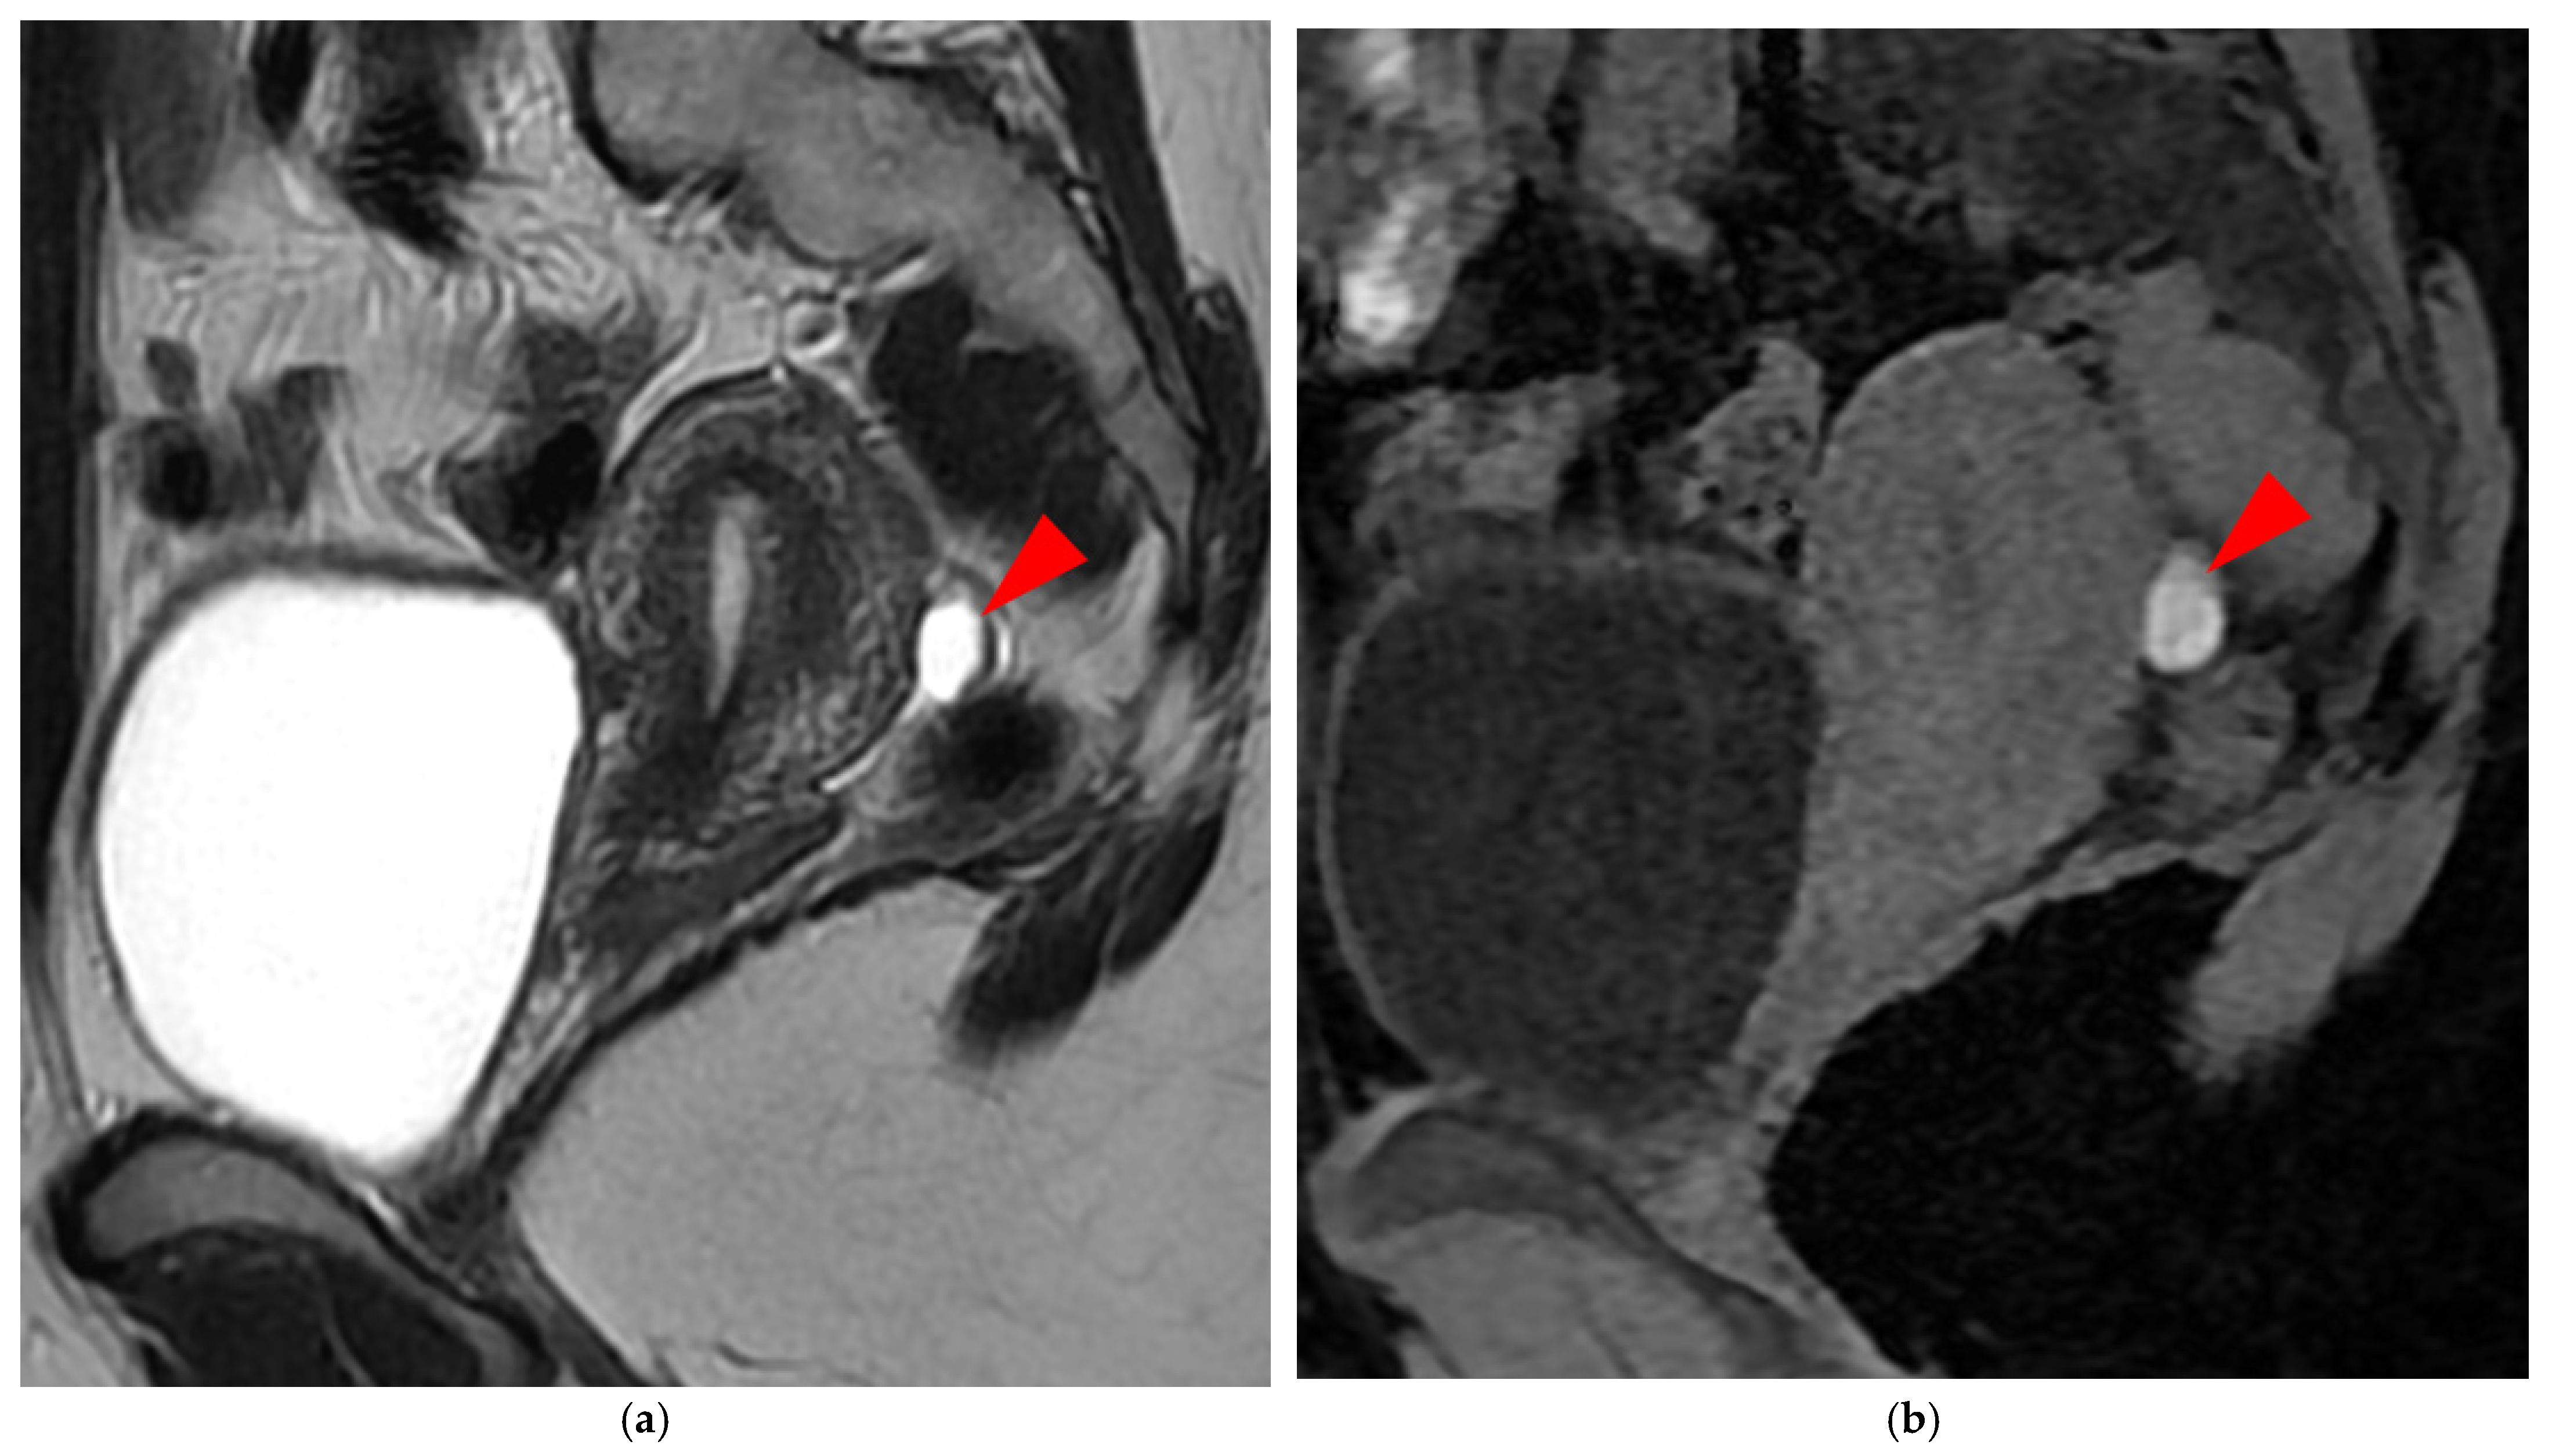

2.1.2. HTD Type 2 USL (PPV = 83%; FPR = 16%)

A type 2 USL (Figure 2) is visible on MRI scans as a curvilinear T2 hypointense structure that mainly originates from the posterior uterine wall at the uterocervical junction, where the torus uterinus is located, and courses dorsocranially toward the sacrum. A type 2 USL is either visible but not measurable due to its minimal thickness (i.e., ≤1 mm), or visible and measurable but thin (i.e., between 1 mm and 2 mm, inclusive of 2 mm). It appears smooth with regular margins and often displays a longitudinally tapering shape.

Figure 2. Pelvic MRI scans of five patients with visible but thin (≤2 mm), smooth, and regular USLs (HTD type 2). (a) Sagittal T2WI: right USL (arrowhead). (b) Sagittal T2WI: right USL (arrowhead). (c) Axial T2WI: right USL (arrowhead). (d) Axial T2WI: left and right USLs (arrowheads). (e) Axial T2WI: right USL (arrowhead).